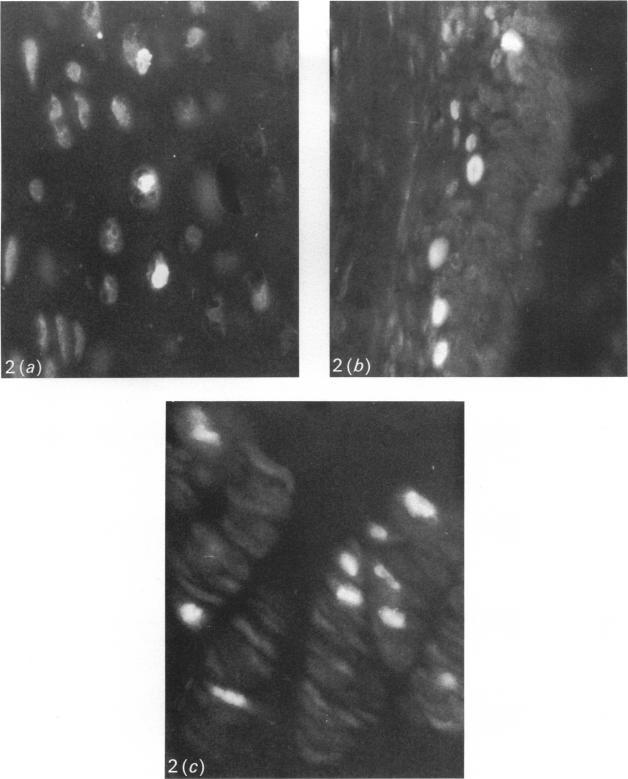

The in situ growth of the ribs at the costochondral junction was examined by 2 methods. In the first, 3 threads were tied around the 5th, 6th or 7th ribs of 20-d-old rats. The first thread was located around the bony part of the rib close to the costochondral junction, the second around the cartilaginous part the same distance away from the junction, and the third also around the cartilaginous part but further away. The distances between the threads were measured at 20 and 40 d and were found to have increased considerably. In the second part, an immunohistochemical method using bromodeoxyuridine was employed to detect proliferating cells at the costochondral junction. The most active cell proliferation was observed in the proliferative zone, but mitoses were also noticed in the germinative zone. The results provide further evidence that the growth potential of costochondral grafts used in reconstructive surgery is related to the length of their cartilaginous portion.

采用两种方法研究了肋软骨结合处肋骨的原位生长情况。第一种方法是,在20日龄大鼠的第5、6或7肋周围系3根线。第一根线位于靠近肋软骨结合处的肋骨骨质部分周围,第二根线位于距结合处相同距离的软骨部分周围,第三根线同样位于软骨部分周围但距离更远。在20天和40天时测量线之间的距离,发现其显著增加。在第二部分中,采用使用溴脱氧尿苷的免疫组织化学方法检测肋软骨结合处的增殖细胞。在增殖区观察到最活跃的细胞增殖,但在生发区也注意到有丝分裂。结果进一步证明,重建手术中使用的肋软骨移植物的生长潜力与其软骨部分的长度有关。